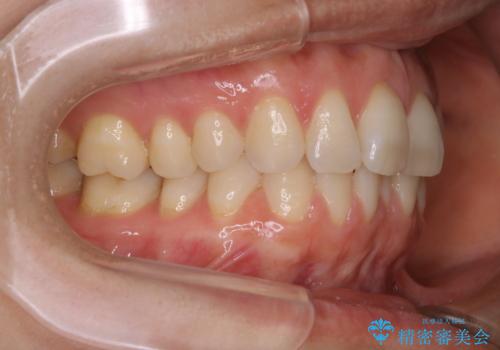

- 下の前歯のがたつきが気になるとの事でご相談にいらした患者様です。

元々はリンガルブラケットをご希望されていましたが、モニター制度を利用してインビザラインによる治療を行いました。

インビザラインFULLで奥歯の噛み合わせから改善させることで、上下の真ん中位置をしっかり合わせることが出来ました。

横顔のシルエットも改善させることができ、大変喜んでいただけました。